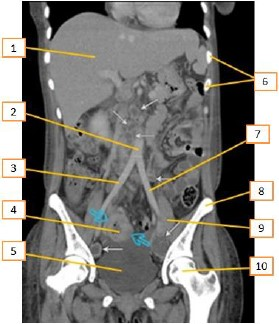

Tomografia computadorizada é um procedimento não invasivo de diagnóstico por imagem que combina o uso de raio-x com computadores especialmente adaptados. É utilizado para criar imagens detalhadas dos mais variados tecidos do corpo humano. O procedimento é realizado através da emissão de raios X rotacionada ao redor do corpo, que, por sua vez e de forma variada, a depender de cada tecido, atenua o feixe de raios-X, que são absorvidos por detectores de radiação, que enviam então os dados para um sistema computacional. Esse sistemconsegue transformar a radiação, através de seus detectores, em um sinal digital no qual se tem a imagem formada muitas vezes mais fidedigna que as imagens radiográficas. Entre os vários assuntos que devem ser conhecidos, a anatomia é fundamental.

Enunciado 4113212-1

Disponível em: https://protocolos-de-tc.webnode.page/abdome/. Acesso em 12/11//2023(Adaptado)

Com base no texto acima e de acordo com a região anatômica apresentada, os números que aparecem na imagem estão corretamente descritos em